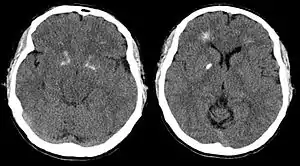

| پرتونگاری مقطعی از مغز بیمار مبتلا به سندرم دی جرج،انباشته شد عن دونی های کلسیم در اطراف بطن و پر شدن از عن گانگلیونها را نشان می دهد . From a case report by Tonelli et al., 2007[1] | |